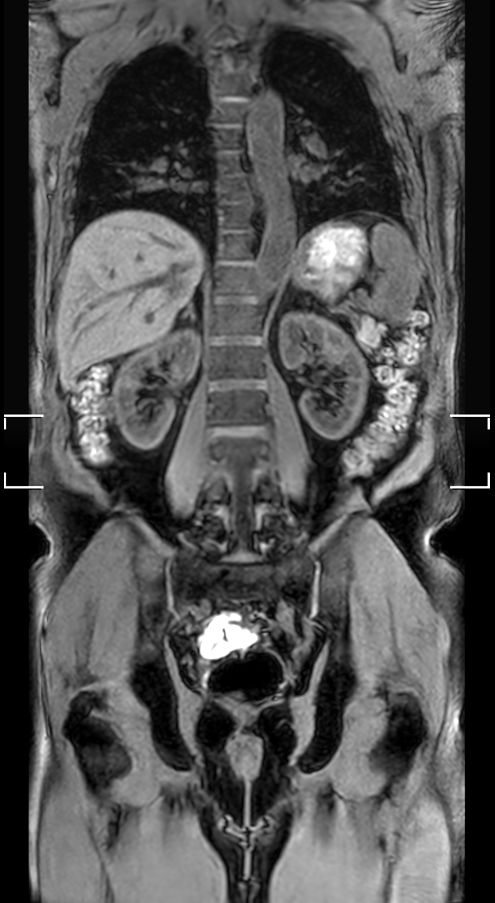

Coronal T2w TSE (1 station)Chest Abdomen - Single coil